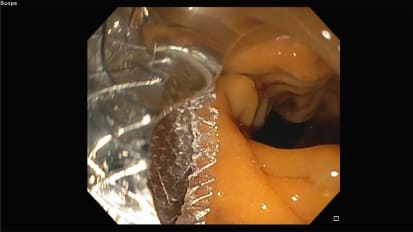

Oh, hi, my name is Daniel, and I'm an assistant professor in biomedical engineering. The general surgery today I would like to share with you some of the world we have been doing in my lab wanted to repair and regeneration using the concept of surgery programming, which is almost like playing with alchemy but with the cells in your body. So I will be discussing strategies that we have developed to convert the skin tissue into insulin producing tissue for the treatment of diabetes, or to convert the skin tissue into brown a deposit issue, which is the good kind of fat for the treatment of obesity. So a few years ago, we developed a groundbreaking technology teaching on the transaction, or TNT, to control the skin tissue plasticity in vivo by the use of nano channels, which are this really tiny conduits with a diameter that's about 100 to 1000 times his mother than that of a human hair. So what we have here is a silicon based chip with nano channels, which can be used to deliver reprogramming genes or signals into skin cells in a highly controlled manner, and the whole procedure takes only about 100 milliseconds. So, depending on the nature of the reprogramming gene or a signal that is used, that skin cell can be converted into another cell type. For example, a new dawn or a blood vessel cell or a pancreatic islet cell essentially using the skin as a bio reactor to grow. Other teachers that could potentially be used to support therapies for the white bar area of conditions. So with funding we got recently from the National Institute of Diabetes and Digestive and Kidney Diseases, we will explore the use of this TNT technology for the development of local sensing, an insulin producing tissue in the skin for the treatment of insulin dependent diabetes. Uh, this is work that is being done in collaboration with Dr Geeta, Castor, Ohio State and Dr Mira Mira at University of Chicago. The goal here, then, is to convert the skin in tow. Better select issue to be able to control blood glucose levels more effectively from the skin in diabetic patients. Pilot studies in diabetic mind show that the skin can be converted into glucose, sensing an insulin producing tissue. As you can see in this micro grafts to the right. Moreover, when we treat the American minds with TNT, we can significantly improved Simic control for up to 11 weeks. As you can see in this chart below again, this is achieved by, ah, one time TNT treatment off the skin, which only lasted about 190 seconds. Finally, this funding will also support studies in collaboration with Dr Stanford from us. You, where the goal is to convert the skin tissue into brown. A deposition, which is the good kind of fat, brown, adipose tissue or bad. It's of interest to us because it is known to help control weight gain or metabolic health. So, of course, it could potentially be uses a therapeutic target for the treatment of obesity. Again, pilot studies indicate that the antique and in those changes in the skin of mice, which are consistent with brandy position specific functionalities. As you can see in these micro grafts to the right and in mice being felt, a high fat diet thesis TNT treatment helped to control weight game very effectively, as you can see in this chart below. And that's all I had to share with you today. Uh, stay tuned for more developments, of course. Stay safe. Everyone by